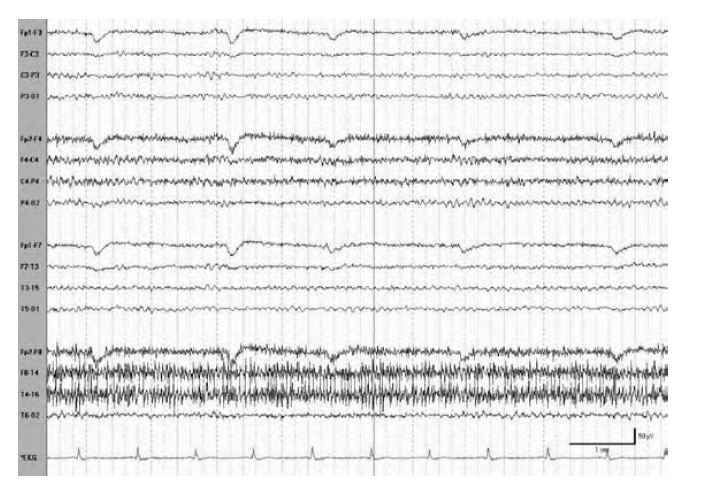

WHAT ARTIFACTS ARE SHOWN PROMINENT DURING REM SLEEP?

Prominent lateral rectus spikes during rapid eye movement (REM) sleep. Spikes occur with rapid eye movements to the left, right, left, and right in the 4th to 6th second.

Each rapid eye movement is associated with a positive potential represented by a phase reversal on eye deviation to the side of the lateral rectus contracting